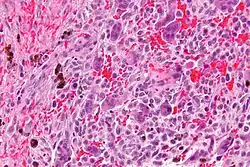

Micrograph of a central giant cell granuloma showing the characteristic giant cells with surrounding cells that have nuclei that are dissimilar to those in the giant cells. H&E stain.

Histology of CGCG shows a lobulated mass composed of vascular connective tissue and multinucleated giant cells (osteoclasts). The giant cells may be diffusely located throughout the lesion or focally aggregate in the lesion, often clustered around hemorrhagic areas hemosiderin deposits. Lobules of the lesion can be separated by fibrous tissue or even thin layer of bone or osteoid that can be seen radiographically. Giant cells are thought to form in response to signals produced by fibroblasts and blood vessels or as a response to cytokines.[2][5]